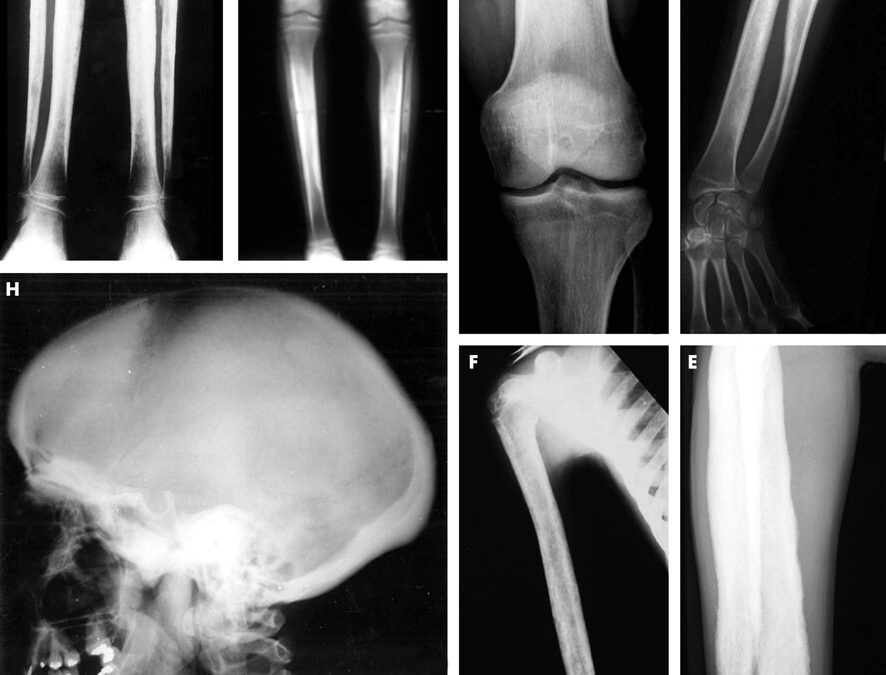

- Anormal Kemik Büyümesi: Engelmann Sendromu, uzun kemiklerin (örneğin, bacak kemikleri) anormal büyümesine neden olabilir. Kemiklerin boyu ve kalınlığı artabilir, bu da kaslara ve eklemlere baskı yapabilir.

- Yüzeyel Kemiklerde Kalınlaşma: Bazı durumlarda, cilt altındaki yüzeyel kemiklerde kalınlaşma ve şişme olabilir.